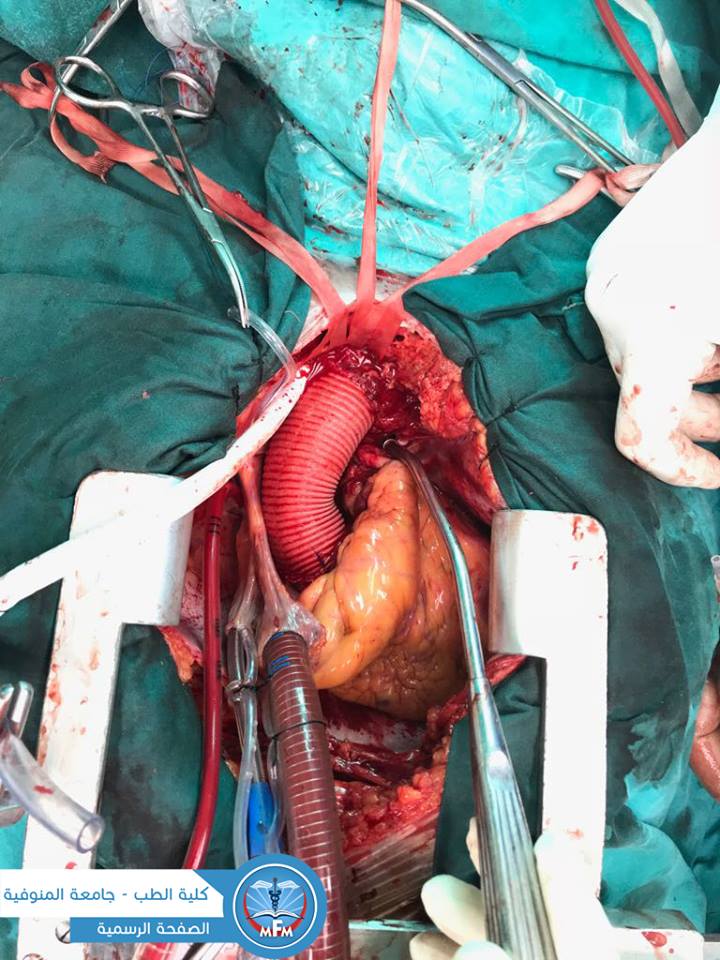

فريـق جراحـى بقسـم جراحـة القلـب و الصـدر بمستشفيـات جامعـة المنـوفيـة ينجـح فـي إنقـاذ حيـاة مريـض بعـد إنفجـار الشريـان الأورطـى بالقلـب

نجـح فـريق جراحـى بقسـم جراحـة القلـب و الصـدر بمستشفيـات جامعـة المنوفيـة برئاسـة الأستـاذ الدكتـور/ رفيـق سليمـان - الأستـاذ المساعـد بالقسـم - مـن إنقـاذ حيـاة مريـض بعـد إنفجـار الشريـان الأورطـى بالقلـب حيـث حـضر مريـض يبلـغ مـن العمـر 59 عامـاً إلـى طـوارئ مستشفيـات جامعـة المنوفيـة كان يعانـى مـن آلام شديـدة بمنطقتـى الصـدر و الظهـر و بعـد إجـراء الفحوصـات الطبيـة مـن موجات صوتيـة علـى القلـب و أشعـة مقطعيـة علـى الشريـان الأورطـى تبيـن وجـود شـرخ و إنفجـار بالشريـان الأورطـى الصاعـد و المستعـرض ممـا يشكل خطـورة بالغـة علـى حيـاة المريـض إذا لـم يتـم التدخـل الجراحـى الفـورى، و علـى الفـور تـم تجهيـز المريـض للعمليـات و تـم تغييـر الشريـان الأورطـى الصاعـد و المستعـرض و إعـادة توصيـل شراييـن الرقبـة و المريـض حاليـاً بحمـد الله بحالـة جيـدة و يخضـع للرعايـة و العـلاج بقسـم جراحـة القلـب و الصـدر بالمستشفيـات الجامعية.

الفريـق الجراحـى المساعـد (أ.د/ إسـلام محـب ، د/ محمـد حجـاج ، د/ هشـام حسـن ، ط/ إبراهيـم خليـل ، ط/ محمـد بقـوش).

فريـق التخديـر (د/ امـل جـودة - ط/ سميـرة )

فـريـق التمريـض بعمليـات جـراحـة القلـب و الصـدر.